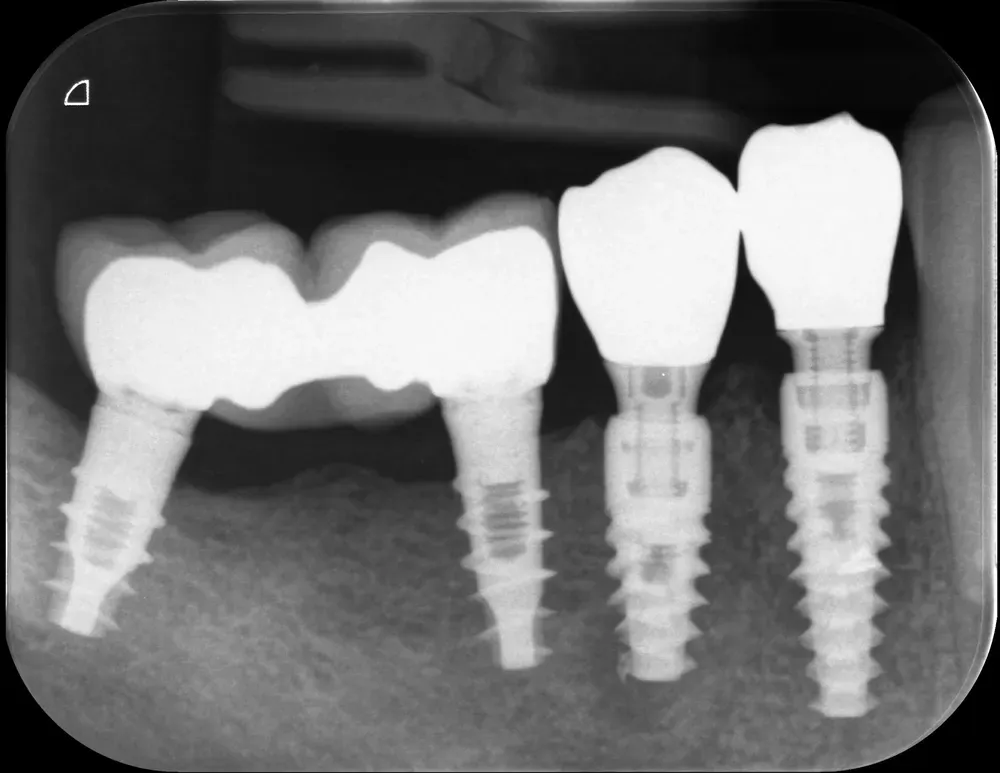

CBCT (Cone Beam CT) pre-operatoria che mostra le estese lesioni ossee dei due premolari inferiori di destra e il ponte su impianti che avevo inserito dieci anni prima.

La radiografia periapicale finale mostra il perfetto successo degli impianti e dell’innesto. Notare come il granuloma apicale del secondo premolare sia guarito perfettamente all’apice dell’impianto. Il granuloma non è stato rimosso. Infatti, nessun tessuto di granulazione deve mai essere rimosso (se non in presenza di purulenza e detriti non altrimenti rimovibili). È un retaggio di epoche lontane e di una visione “meccanicistica” della chirurgia orale ed è privo di fondamento scientifico.